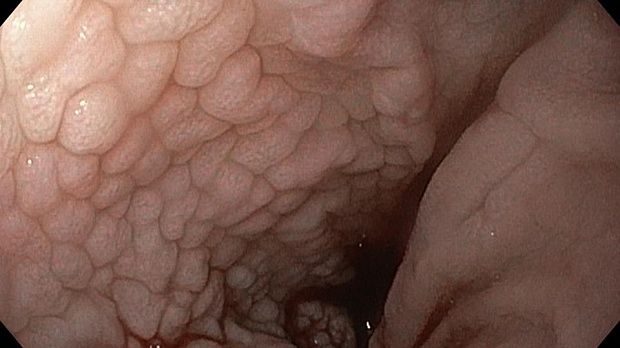

Публикации из социальных сетей: “Cobblestone esophagitis” (эзофагит со слизистой булыжной мостовой)

“Cobblestone esophagitis” (эзофагит со слизистой булыжной мостовой) - редкая эндоскопическая находка и ассоциируется с эозинофильным эзофагитом, кандидозом и пищеводом Барретта у взрослых. Он также может быть найден при тяжелом рефлюкс-эзофагите, вторичен к дистальной обструкции гастроинтестинального тракта. В нашем случае - это пациент после с 9-летним стажем бандажирования кардиального отдела желудка, признаками дуоденостаза, фундальной эрозивной гастропатией, расширением пищевода и уровнем жидкости в нем при горизонтальном положении, грыжи ПОД, эрозивно-язвенном дистальном эзофагите.. Пациент просто пришел удалить полип в прямой кишке и заодно посмотреть, что творится в желудке.... Ацетообеление+NBI+биопсия. ИПП на 3-4 мес и повтор для решения о Барретте.